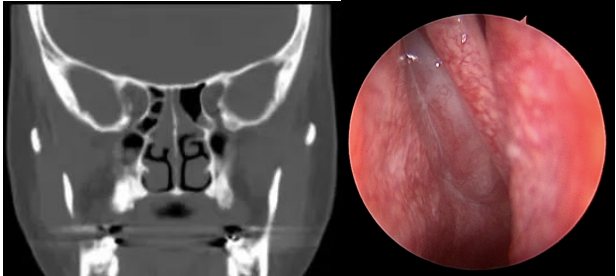

通过鼻内镜检查,刘教授观察到,陈先生上呼吸道双侧鼻腔中鼻道、嗅裂有鼻息肉,软腭平面和舌根平面没有明显狭窄。同时,鼻窦CT显示,陈先生患有双侧鼻窦炎。

于是,阿云来到医院寻求帮助。刘教授详细询问了病情。阿云平时并没有鼻塞、流涕、头痛等症状,嗅觉问题近两年组建加重,偶尔能闻见一点气味。她并没有明确的外伤或上呼吸道感染史。体检中,并无发现鼻腔内有明显的异常,但嗅觉检测显示阿云的嗅觉中度损失。在其后的鼻内镜检查中,有了重要发现——在双侧鼻腔的最上部,也就是嗅裂区域,发现了息肉!刘教授告诉她,鼻息肉可能是导致她嗅觉下降的最大元凶。

深思熟虑后,阿云选择了手术治疗。术前的鼻窦CT检查,不出所料,阿云有全组鼻窦炎,尤其是筛窦炎。刘教授为她进行了微创手术-鼻内镜下鼻窦开放与鼻息肉切除术。术后,阿云恢复得很好,一周后就可以闻到气味了,一个月后阿云的嗅觉基本恢复到正常状态。

>>>刘教授小课堂

鼻腔嗅觉区域位于鼻腔的顶部(蓝色虚线方框圈出)非常狭窄的区域。当局部病变时,如局部肿胀、小息肉、局部分泌物等,可能并不影响呼吸、也没有鼻塞等症状,但嗅觉功能却有可能发生变化。正如阿云这个病例。虽然本病例经过手术等综合处理,患者嗅觉恢复了,但是患者还是要坚持复查与治疗,如生理盐水洗鼻、鼻喷激素等,日常预防感冒。若嗅觉再次下降一定要及时就医。